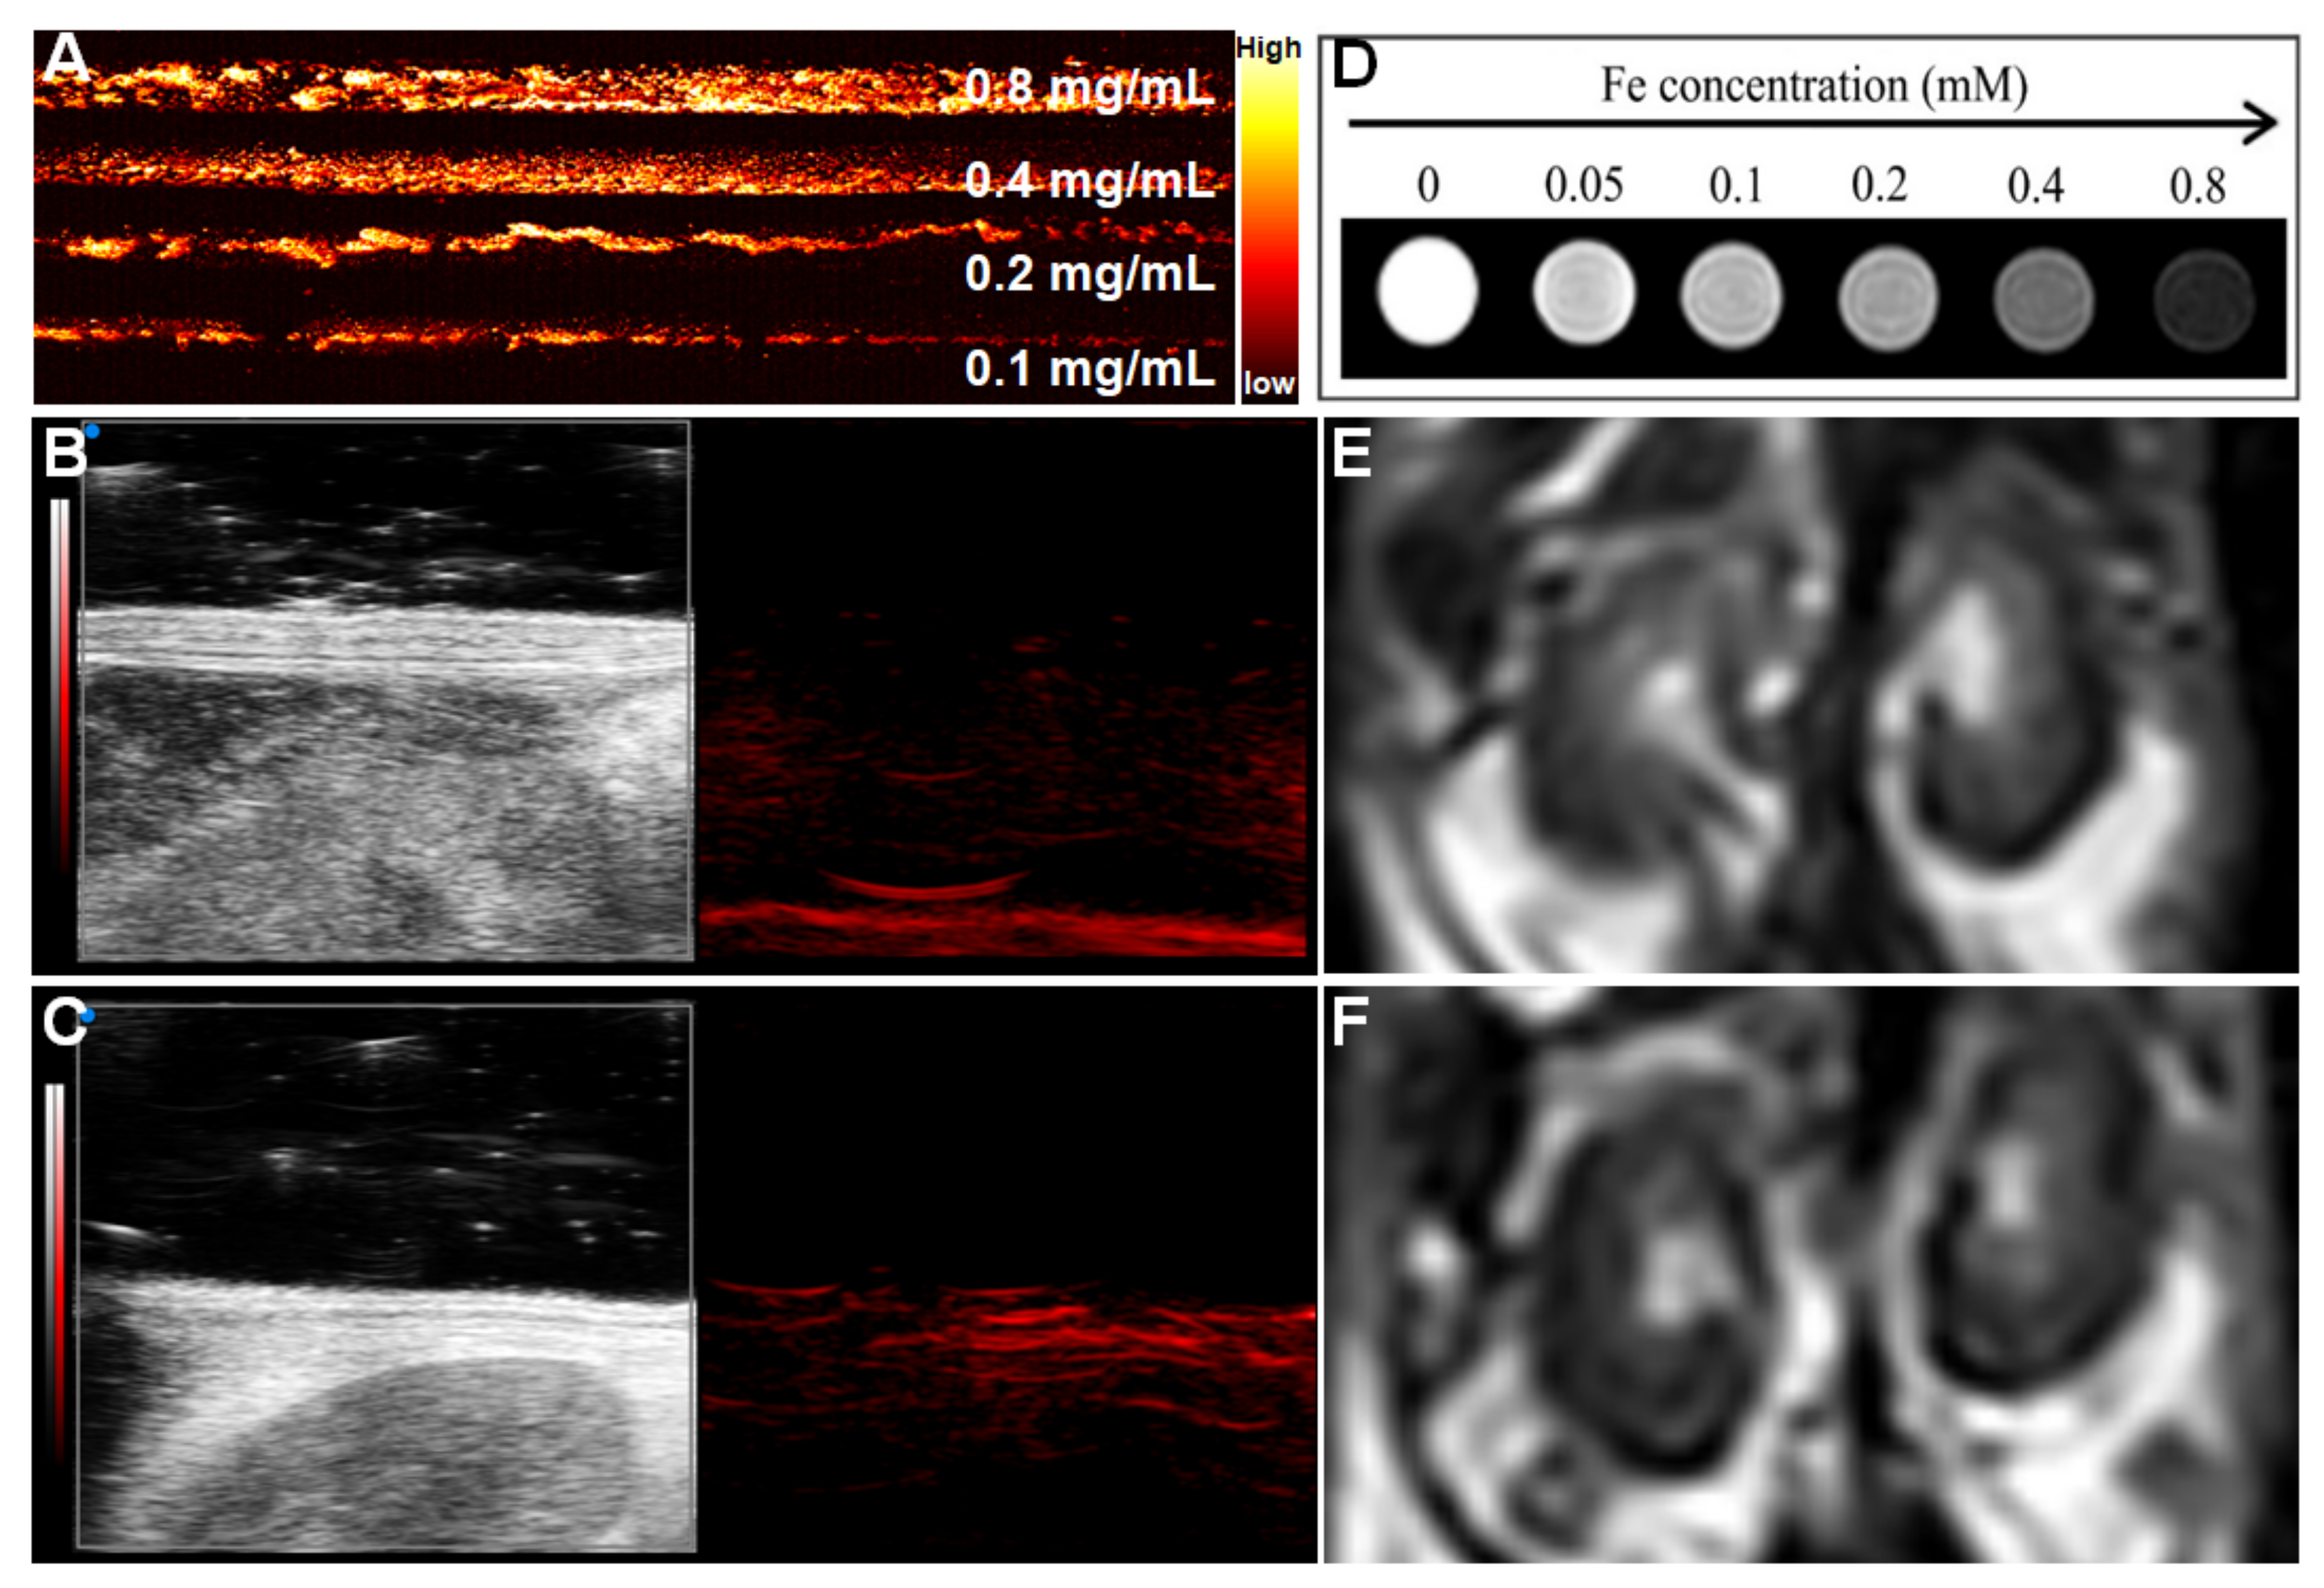

3.2. PA and MR Dual-Mode Image Tracking